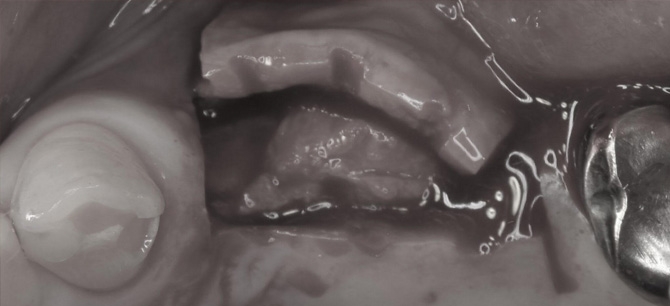

抜歯後の状態です。

カラーだと見えにくいですが、モノトーンにしてみると、抜歯した部位の先端部分に小さい穴が空いていることが分かります。

この穴は副鼻腔(上顎洞)に繋がっています。

従来は、口腔と副鼻腔が繋がってしまうのは、インプラント治療失敗の原因になると考えられてきました。

しかし、最新の知見では、小さい穴であれば問題ないと言われています。